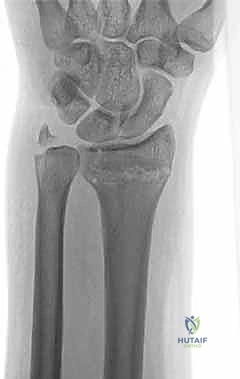

استخدام الأشعة السينية في التشخيص

1. الأشعة السينية (X-rays): بوضعيات متعددة (أمامية خلفية، وجانبية دقيقة). الوضعية الجانبية الحقيقية (True Lateral) حاسمة لاكتشاف أي خلع جزئي في المفصل (DRUJ).

2. الأشعة المقطعية ثلاثية الأبعاد (3D CT Scan): تُستخدم في الكسور المفتتة أو كسور رأس الزند المفصلية المعقدة، حيث تعطي خريطة دقيقة للجراح قبل الدخول لغرفة العمليات.